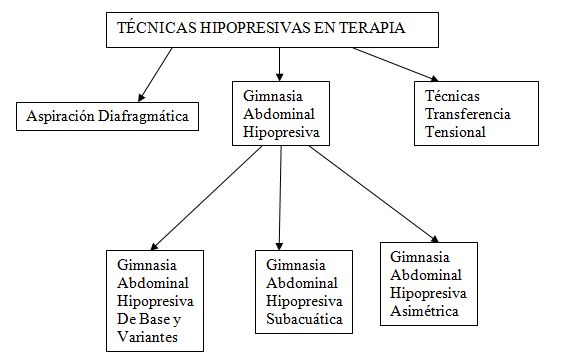

Existen diversas técnicas dentro del Método Hipopresivo en función del

objetivo y de la persona. Se agrupan en dos grandes grupos: Hipopresivos Terapia

e Hipopresivos en sala de Fitness y Deporte.

Desde el punto de visa terapéutico hay tres grupos:

Figura

1. Clasificación de las Técnicas Hipopresivas en Terapia